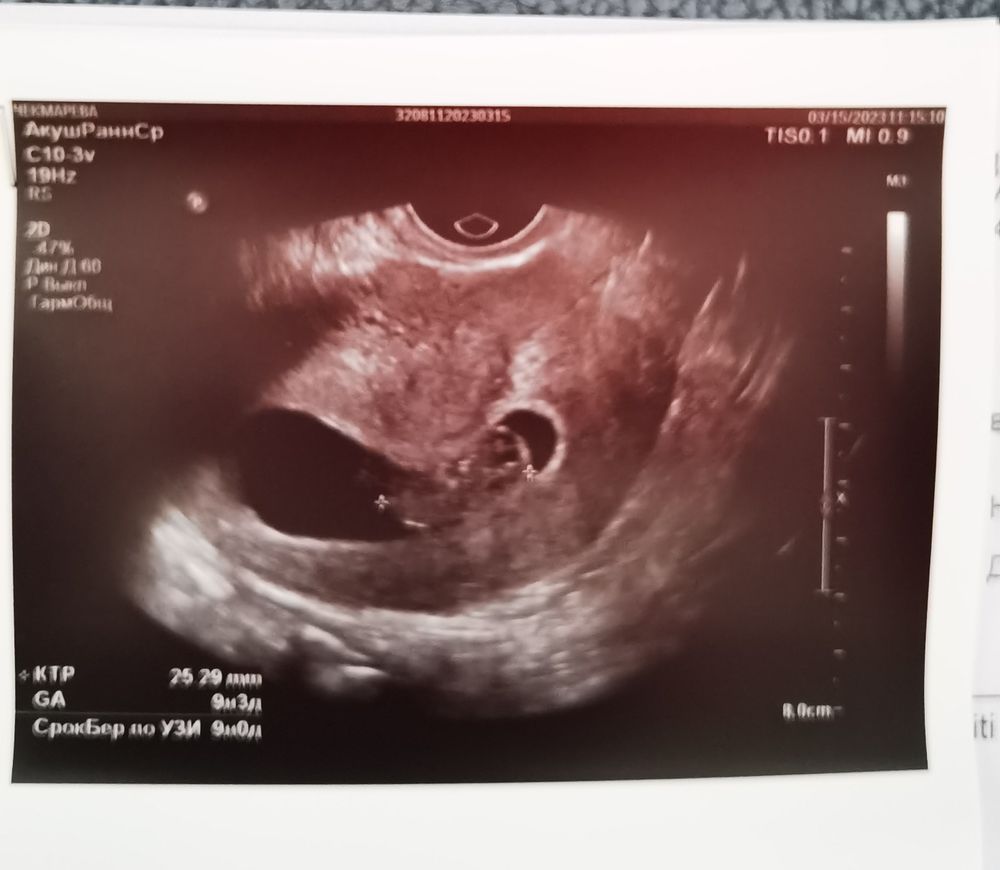

Была вчера на контрольном узи у своей хорошей Гини. ПЯ неправильной формы - либо сильный тонус, либо миома, хотя чётких границ не просматривается. Я очень переживаю, не поверит ли малышу эта временная деформация, не расплющит ли его😵 не могу ускопоиться(( пью магний 400мг, врач вчера ещё назначила папаверин 1 нед минимум. Особо не двигаюсь и так, работаю на удаленке, тяжёлого не таскаю. Плюс ещё увидели следы 2х старых гематом близко к ПЯ, поэтому видимо и кровила на 17дпп.

В остальном по показателям все отлично, чсс 178, ручками ножками двигался, глазки и мозг видели

Хотя когда 4 марта была на УЗИ у Ре, она не увидела остатки гематом и ПЯ было правильной формы, ставила только небольшой тонус.